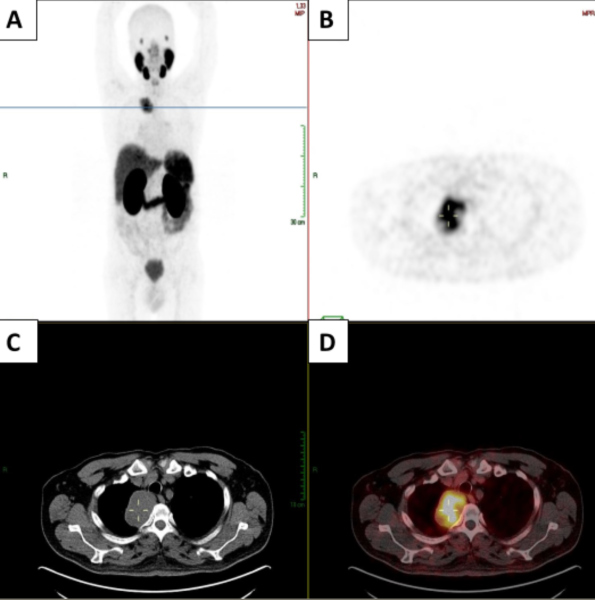

Se trata de un paciente masculino de 62 años con antecedente de adenocarcinoma de próstata Gleason 3+4 con recaída tumoral por elevación de PSA (0,88 ng/ml), por lo cual se solicitó PET/CT con 68Ga-PSMA. El estudio evidenció una masa con expresión de PSMA en el mediastino posterior, la cual fue resecada y el reporte de la patología fue un tumor derivado de la vaina nerviosa periférica (schwannoma). En el resto del rastreo realizado no se evidenciaron otras lesiones con expresión de PSMA. En el seguimiento, el paciente presenta aumento de los niveles de PSA (1,6 ng/ml) por lo que se decide realizar nuevo PET/CT con 68Ga-PSMA, el cual muestra la desaparición de la masa mediastinal descrita anteriormente, sin evidencia de otras lesiones. Se presentan las imágenes del PET/CT con 68Ga-PSMA inicial (Fig. 1) y el control posterior a la resección del tumor (Fig. 2).